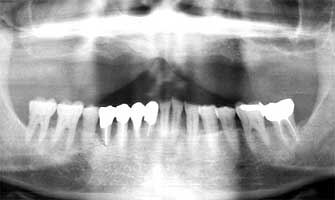

Fig. 14 Ms F 17 years later 33 years old.

As a result of continuing monthly maintenance the possibility of advancement of gingivitis has not occurred.

Ms F 16 years old at the time of the first medical examination. Woman (Fig. 13-14)

She has undergone gingivitis treatment two years ago. However a lot of tartar of the edge of the gum was found on her teeth at the time of first medical examination. Her 5 year older sister already had a tooth in the final stage of gingivitis. Ms F therefore had the strong possibility of also developing to the final stage. Taking note of this I believed her to be of juvenile gum disease. As a result of consistently continuing to remove the tartar her tendency to develop gingivitis has not occurred even 17 years later. Even her older sister who lost a tooth to gingivitis, 16 years later has maintained and retained all other teeth.